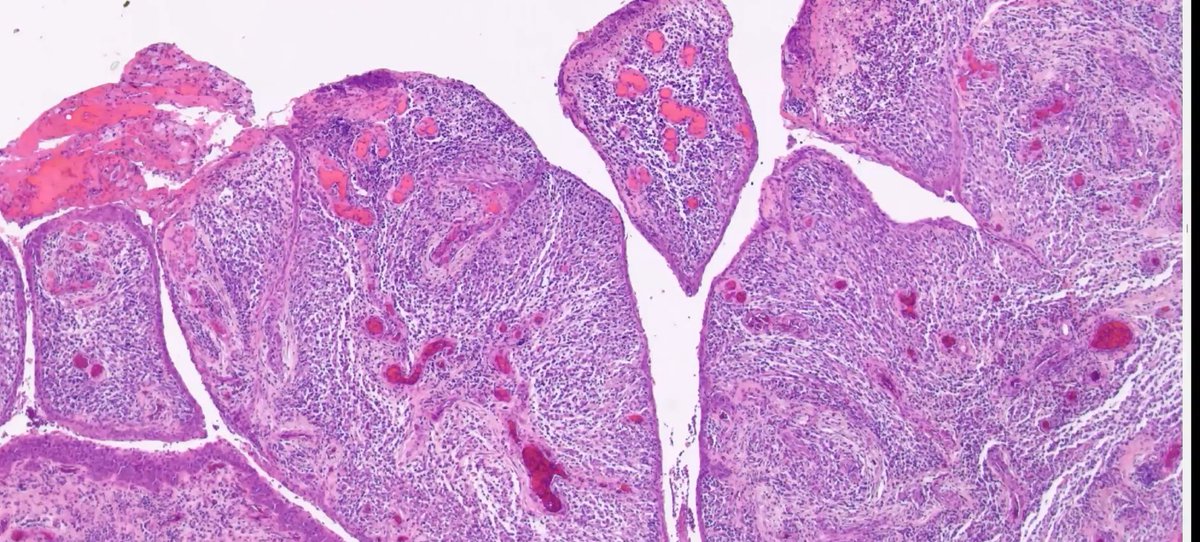

Answer:  This is a porokeratoma! At low power you see diffuse wave-like, columnar cornoid lamella with an abrupt transition from normal. Read more about this entity here: onlinelibrary.wiley.com/doi/10.1111/cu…

#COTW with PGY1 @meredithkherman featuring a variant in #dermpath.  Shave biopsy of groin lesion. What histologic features do you see? What is your differential diagnosis?

UMichPath's tweet image. #COTW with PGY1 @meredithkherman featuring a variant in #dermpath.  Shave biopsy of groin lesion. What histologic features do you see? What is your differential diagnosis?